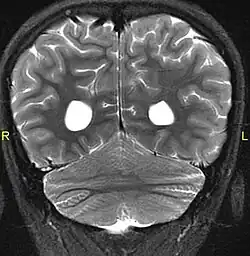

Aside from the physical characteristics of the eyes there is also less sensation in the eyes when stimulated.[4] The eyes also show low motor control (ataxia).[4] Along with ataxia comes a lack of coordination or ability to judge the distance of objects (dysmetria).[6] MRIs show a constant feature of rhombencephalosynapsis–a condition marked by the absence or partial absence of the cerebellar vermis and varying degrees of fusion in the cerebellum in every case of Gómez–López-Hernández syndrome.[4][7][8] Also absent are the trigeminal nerve of the trigeminal cave and the foramen rotundum, causing abnormal sensations on the forehead and the corneas.[6][8] One Gómez–López-Hernández syndrome case in Japan also presents fever-induced seizures.[9] Others may or may not present with non-fever-induced seizures.[4] Malformations of motor centers in the brain cause reduced muscle strength (hypotonia).[8] Eleven of fifteen people in one study showed moderate-to-severe intellectual disability.[6] In cases where it has been noted, head nodding is present.[6] Hydrocephalus and enlargement of the ventricular system is consistently present.[6] A reduced corpus callosum is present in some cases (agenesis of the corpus callosum).[6]

MRI showing fusion of cerebellar hemispheres common in GLH syndrome